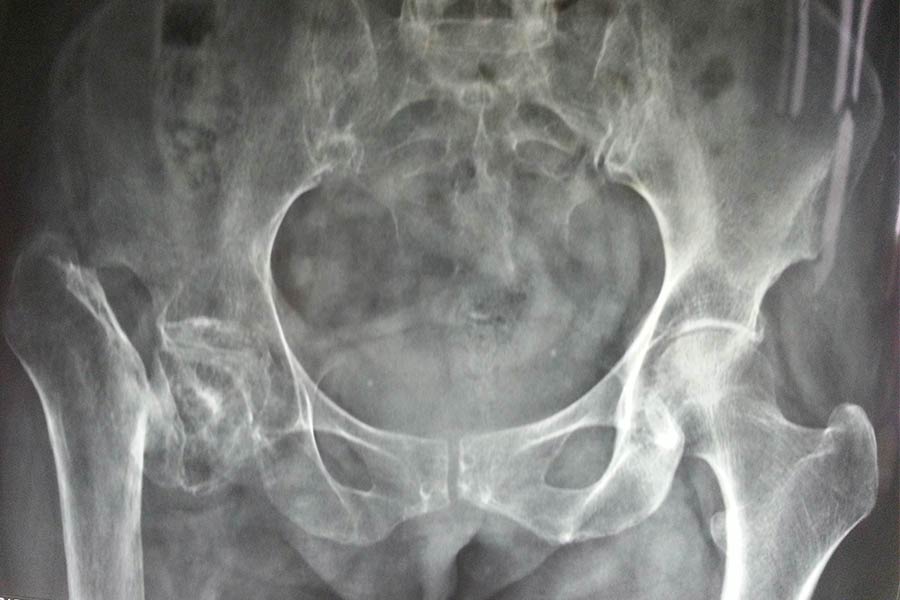

Total Hip Replacement

Difficult Replacement

Case 1